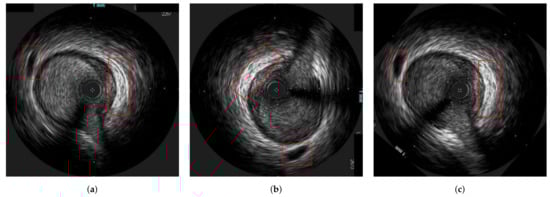

3.1. Data Preprocessing

3.3. Axial Registration